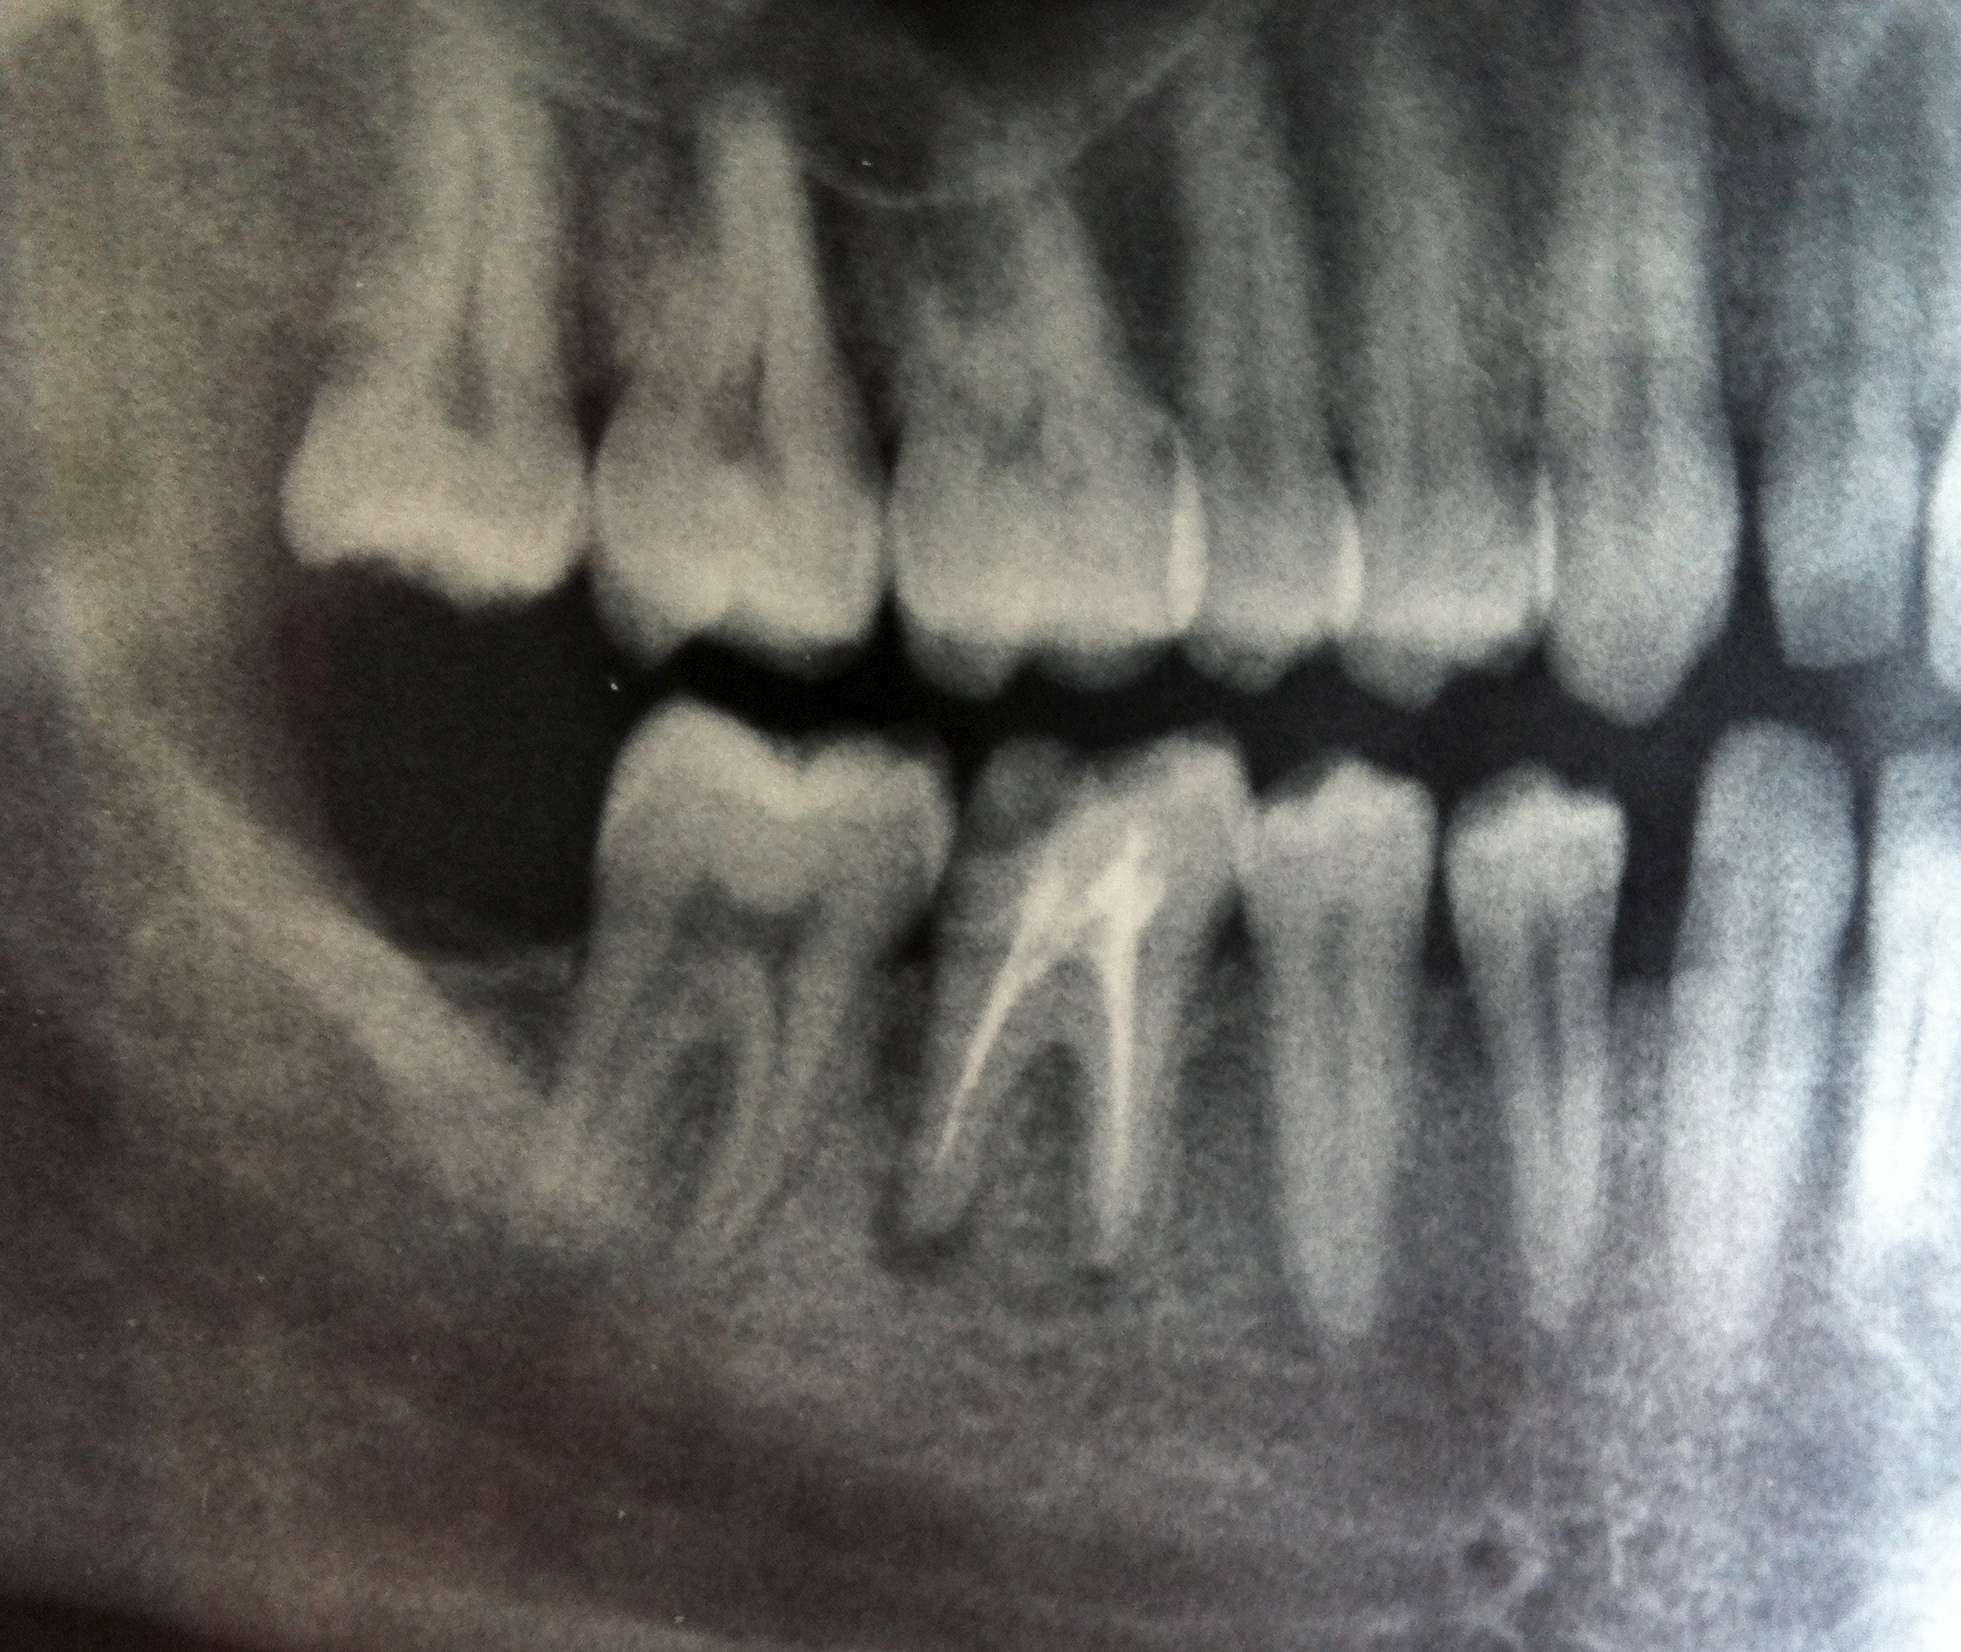

Salve, volevo porvi questa domanda: Venerdì 7 settembre mi è stato chiuso con ricostruzione della corona dopo essere stato devitalizzato (praticamente in 3 sedute compresa l'ultima) il dente n.6 situato nella parte inferiore destra, dovrebbe essere il molare. Il dentista mi ha fatto una sola radiografia nel suo studio, dalla quale mi

Leggi tutto